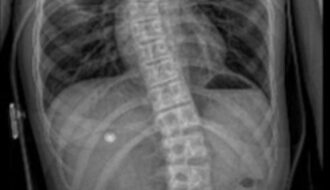

Skolioza u Dzieci: Objawy, Przyczyny i Sposoby Leczenia

Czy Twoje dziecko ma krzywe plecy? Podejrzewasz skoliozę, ale nie wiesz, od czego zacząć? Skolioza u dzieci to coraz częstszy problem, który – odpowiednio wcześnie wykryty – można skutecznie leczyć. … Czytaj dalej Skolioza u Dzieci: Objawy, Przyczyny i Sposoby Leczenia